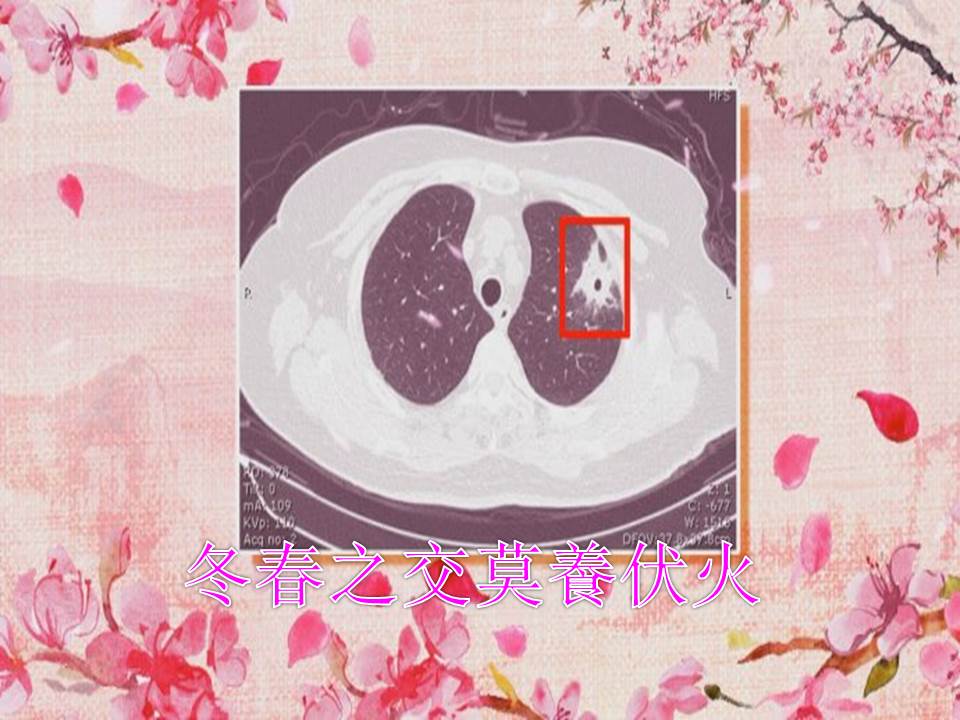

冬春之交莫养伏火